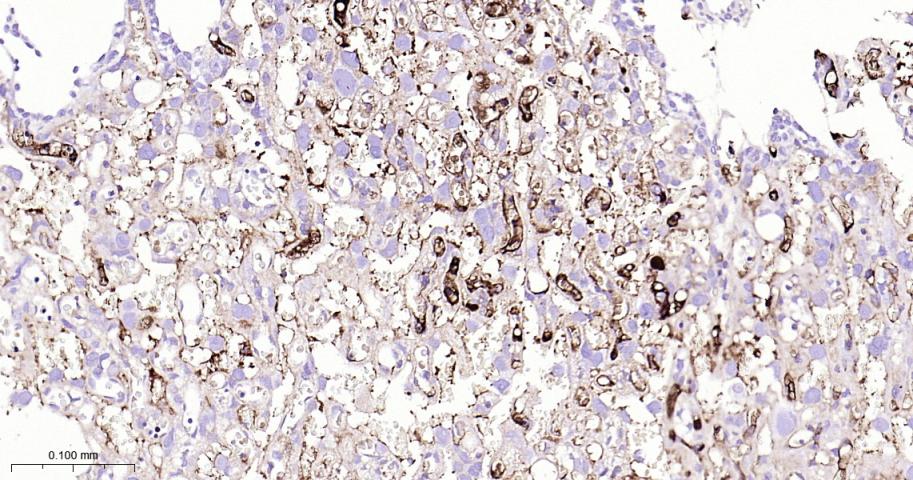

Paraformaldehyde-fixed, paraffin embedded Rat Placenta; Antigen retrieval by boiling in sodium citrate buffer (pH6.0) for 15 min; Antibody incubation with Fibrinogen alpha chain Monoclonal Antibody, Unconjugated(bsm-62182R) at 1:100 overnight at 4°C, followed by conjugation to the bs-0295G-HRP and DAB (C-0010) staining.

Paraformaldehyde-fixed, paraffin embedded Human Placenta; Antigen retrieval by boiling in sodium citrate buffer (pH6.0) for 15 min; Antibody incubation with Fibrinogen alpha chain Monoclonal Antibody, Unconjugated(bsm-62182R) at 1:100 overnight at 4°C, followed by conjugation to the bs-0295G-HRP and DAB (C-0010) staining.

Paraformaldehyde-fixed, paraffin embedded Human Lung; Antigen retrieval by boiling in sodium citrate buffer (pH6.0) for 15 min; Antibody incubation with Fibrinogen alpha chain Monoclonal Antibody, Unconjugated(bsm-62182R) at 1:100 overnight at 4°C, followed by conjugation to the bs-0295G-HRP and DAB (C-0010) staining.

Paraformaldehyde-fixed, paraffin embedded Rat Lung; Antigen retrieval by boiling in sodium citrate buffer (pH6.0) for 15 min; Antibody incubation with Fibrinogen alpha chain Monoclonal Antibody, Unconjugated(bsm-62182R) at 1:100 overnight at 4°C, followed by conjugation to the bs-0295G-HRP and DAB (C-0010) staining.

Paraformaldehyde-fixed, paraffin embedded Mouse Lung; Antigen retrieval by boiling in sodium citrate buffer (pH6.0) for 15 min; Antibody incubation with Fibrinogen alpha chain Monoclonal Antibody, Unconjugated(bsm-62182R) at 1:100 overnight at 4°C, followed by conjugation to the bs-0295G-HRP and DAB (C-0010) staining.